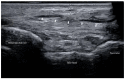

Adult acquired flatfoot deformity (AAFD) is a disorder caused by repetitive overloading, which leads to progressive posterior tibialis tendon (PTT) insufficiency. It mainly affects middle-aged women and occurs with foot pain, malalignment, and loss of function. After clinical examination, imaging plays a key role in the diagnosis and management of this pathology. Imaging allows confirmation of the diagnosis, monitoring of the disorder, outcome assessment and complication identification. Weight-bearing radiography of the foot and ankle are gold standard for the diagnosis of AAFD. Magnetic Resonance Imaging (MRI) is not routinely needed for the diagnosis; however, it can be used to evaluate the spring ligament and the degree of PTT damage which can help to guide surgical plans and management in patients with severe deformity. Ultrasonography (US) can be considered another helpful tool to evaluate the condition of the PTT and other soft-tissue structures. Computed Tomography (CT) provides enhanced, detailed visualization of the hindfoot, and it is useful both in the evaluation of bone abnormalities and in the accurate evaluation of measurements useful for diagnosis and post-surgical follow-up. Other state-of-the-art imaging examinations, like multiplanar weight-bearing imaging, are emerging as techniques for diagnosis and preoperative planning but are not yet standardized and their scope of application is not yet well defined. The aim of this review, performed through Pubmed and Web of Science databases, was to analyze the literature relating to the role of imaging in the diagnosis and treatment of AAFD.